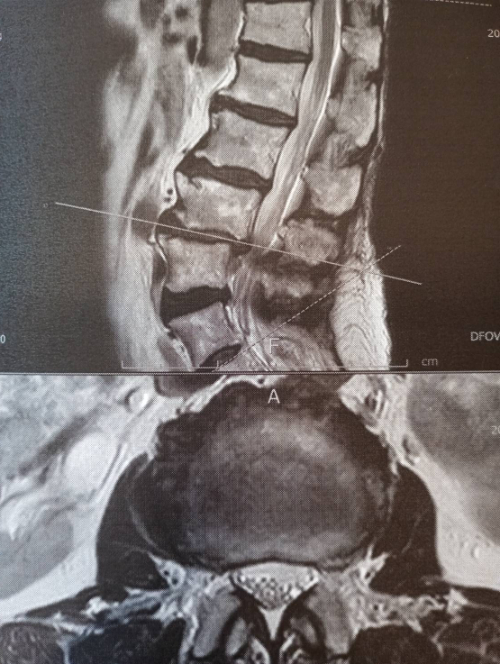

白く映っている部分が脊髄神経で数か所狭くなっている箇所が見られます。変形狭窄とヘルニアによる脊髄神経(もしくは位置的には馬尾神経)圧迫があります。

神経の圧迫があると画像では判断します。(臨床症状と一致)